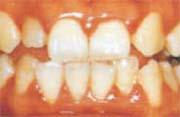

歯肉炎の歯肉

(1)やや丸い…歯と歯の間はやや丸みを帯びている

(2)赤い

(3)柔らかい

(4)出血…さわると血が出る、痛くないのに血が出る